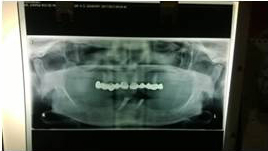

Pre Operation X-ray

Placement of Bone Grafting

Use of Bone Graft & GTR membrane for an Implant